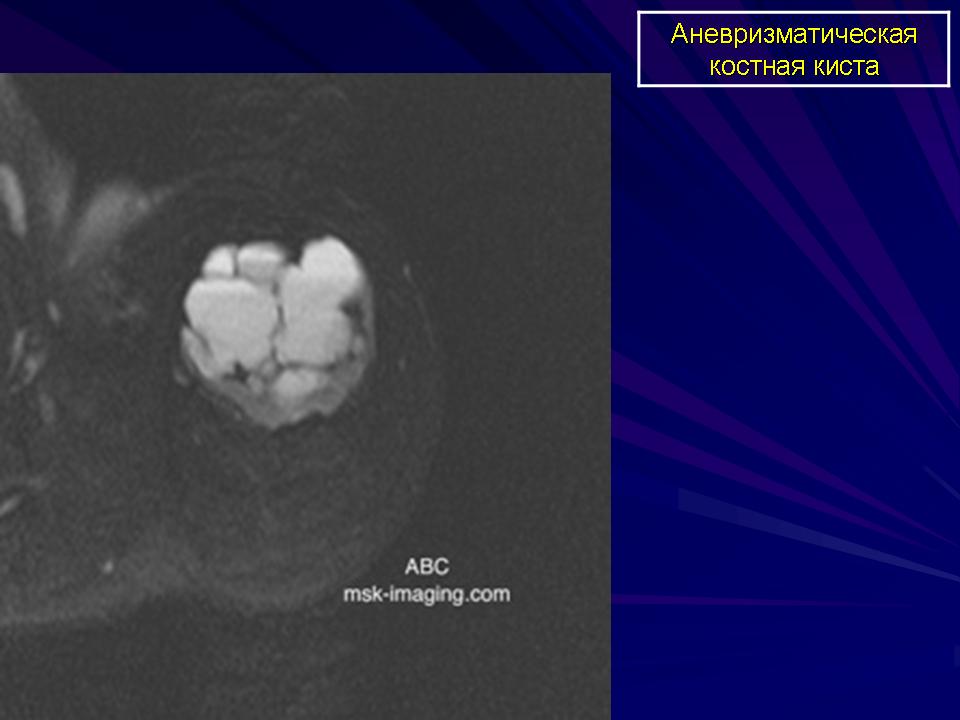

Аневризматическая костная киста.